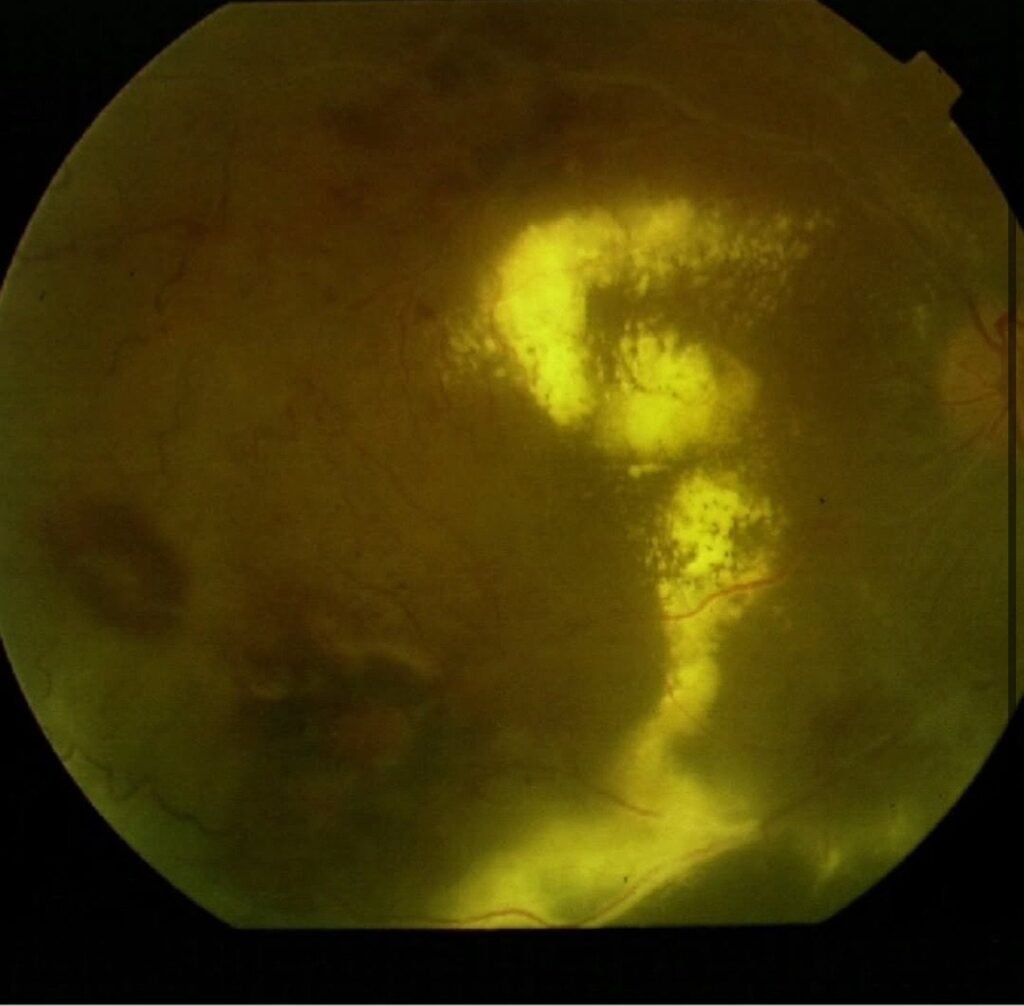

Case Study Highlight

The patient in this case—shared by Dr. Gil Calvão-Santos—was a woman in her 40s who presented with sudden vision loss in the right eye. The examination revealed a vitreous hemorrhage, a hallmark of the proliferative stage of Eales disease. Interestingly, she had asymmetrical disease, with her right eye more severely affected, resulting in significantly reduced vision.

This case is notable not only for the patient’s age and gender, which are atypical for Eales disease, but also for the unilateral severity, underscoring how unpredictable the disease can be.